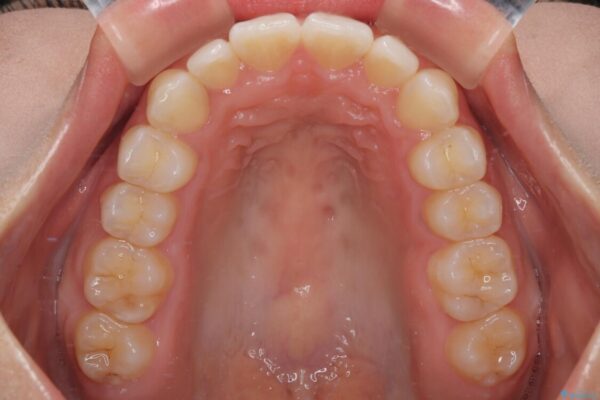

治療後

• 目立ちにくい表側装置で1年完了!狭いアーチを側方拡大し前歯のデコボコを整えた症例 治療後画像

前歯が自然なアーチにきれいに並び、正中(上下の中心線)も整い、咬み合わせも良好です。

側方拡大することで、非抜歯であるにも関わらず前歯が前方に出ることなく、バランスの良い仕上がりとなりました。